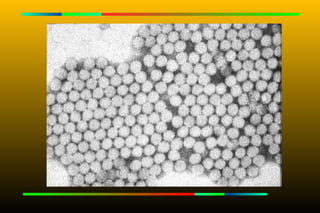

Hepatitis A virus

Structure

Small, non-

enveloped

icosahedral

particle,



27 nm in

diameter

    ssRNA

Structure  Small, non- enveloped icosahedral particle,  27 nm in diameter  ssRNA